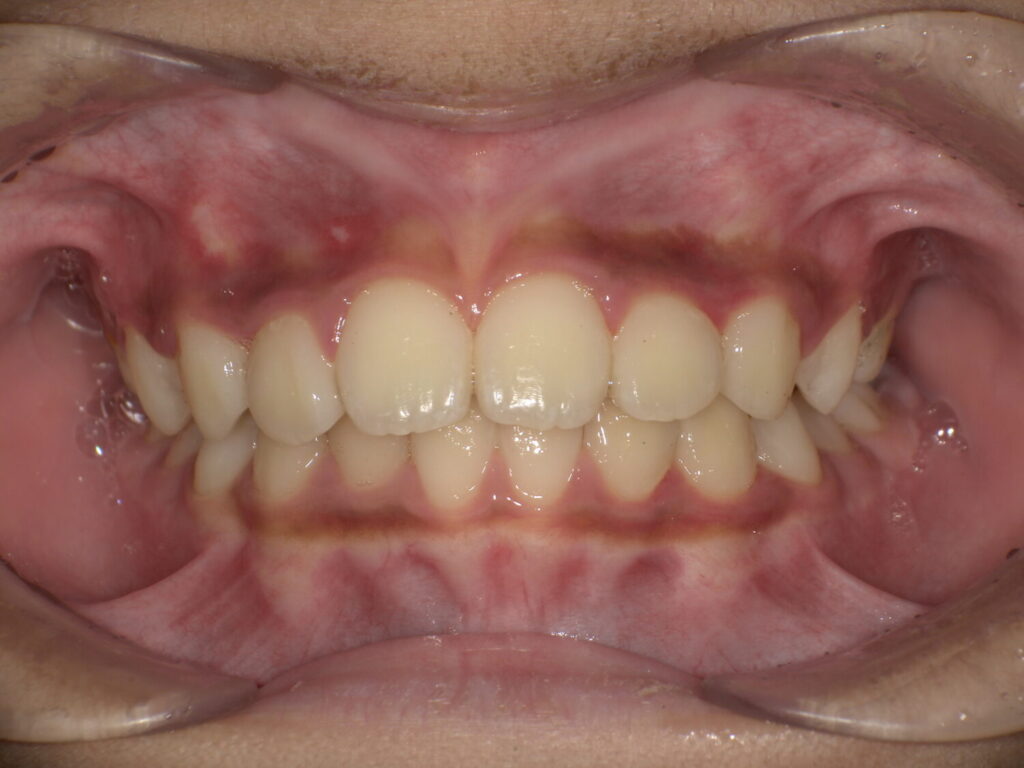

3番目の歯が抜けて生え変わる頃にグッと噛み合わせが変化して、下の歯も並びました。

マウスピースとアクティビティーでここまで変化しました!

また、前歯が大きいと言われていたことが気になっていましたが顎も大きくなって正しく並んでいると大きく感じなくなります。